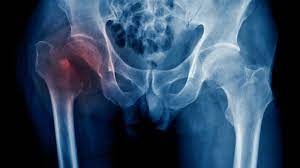

Hip Pain

Hip pain is a common complaint that can be caused by a wide variety of problems. The precise location of your hip pain can provide valuable clues about the underlying cause.

Problems within the hip joint itself tend to result in pain on the inside of your hip or your groin. Hip pain on the outside of your hip, upper thigh or outer buttock is usually caused by problems with muscles, ligaments, tendons and other soft tissues that surround your hip joint.Hip Pain Treatment reduce the pain in hip joint.